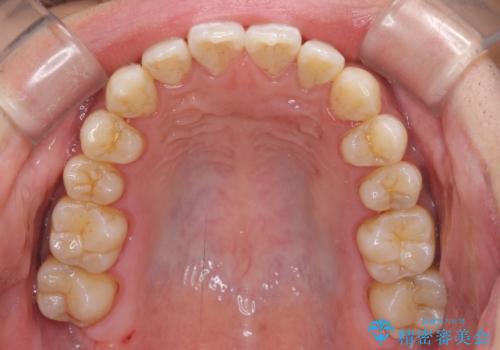

下顎前歯と上顎の部分矯正

- 上下の前歯の叢生を気にして来院された患者様です。

前歯のみの矯正治療を希望でしたが、上顎臼歯が舌側転位していたため、上顎は全体を、下顎は前歯のみを矯正治療することとしました。

矯正治療は上下全顎を行うことが大前提ですが、費用などの点から、今回は部分矯正を選択することとなりました。